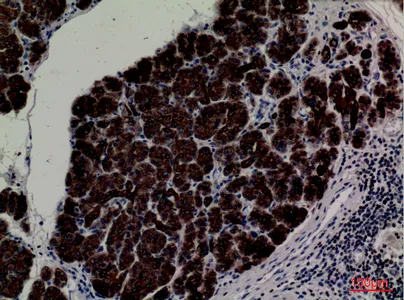

alpha 1 Fetoprotein Rabbit Polyclonal Antibody

Cat: APRab00486

Size1:50μl Price1:$150

Size2:100μl Price2:$280

Size3:500μl Price3:$1200

Size2:100μl Price2:$280

Size3:500μl Price3:$1200